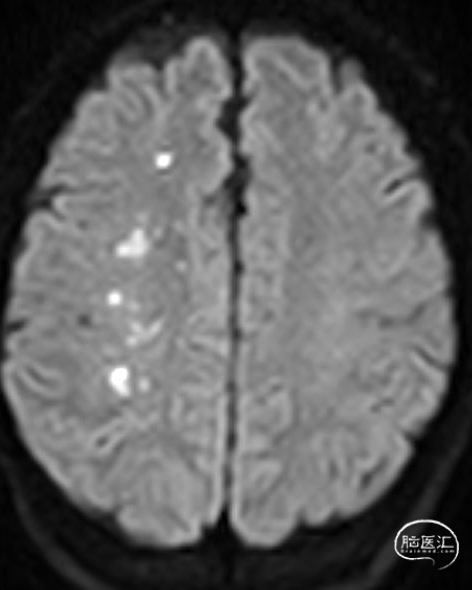

02、术前影像

为进一步评估梗死大小和颅内情况,磁共振显示颈内动脉闭塞,小的核心梗死。